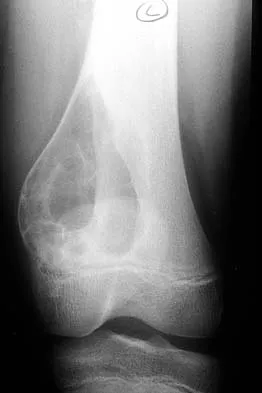

A 16-year-old girl has had pain in the left groin for the past 4 months. She notes that the pain is worse at night; however, she denies any history of trauma and has no constitutional symptoms. There is no history of steroid or alcohol use. Examination reveals pain in the left groin with rotation of the hip. There is no associated soft-tissue mass. A radiograph and MRI scan are shown in Figures 32a and 32b, and biopsy specimens are shown in Figures 32c and 32d. What is the most likely diagnosis?

Explanation

Based on the epiphyseal location and sharp, well-defined borders, the radiograph suggests chondroblastoma. Histologically, multinucleated giant cells are scattered among mononuclear cells. The nuclei are homogenous and contain a characteristic longitudinal groove. Although not seen here, "chicken-wire calcification" with a bland giant cell-rich matrix is also typical for chondroblastoma. Clear cell chondrosarcoma occurs in epiphyseal locations but has a more aggressive histologic pattern and occurs in an older age group. Giant cell tumors occur in the epiphysis but have a more uniform giant cell population histologically. Aneurysmal bone cyst often results in bone remodeling and has a different pathologic appearance. Osteonecrosis has a typical histologic pattern of empty lacunae and necrotic bone. Springfield DS, Capanna R, Gherlinzoni F, et al: Chondroblastoma: A review of seventy cases. J Bone Joint Surg Am 1985;67:748-755. Simon M, Springfield D, et al: Chrondroblastoma: Surgery for Bone and Soft Tissue Tumors. Philadelphia, PA, Lippincott Raven, 1998, p 190.